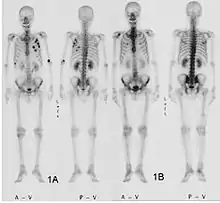

Fracture pathologique du bras gauche sur une métastase osseuse de cancer du sein Scintigraphie corps entier avec 99mTc-HDP de la patiente avec une fracture du bras due à une métastase du cancer du sein

Scintigraphie corps entier avec 99mTc-HDP de la patiente avec une fracture du bras due à une métastase du cancer du sein

Scintigraphie osseuse

La scintigraphie osseuse est actuellement encore le meilleur moyen de diagnostic des métastases osseuses. Ce procédé est relativement sophistiqué, coûteux et soumis à quelques limites diagnostiques[90]. Contrairement à la radio, on peut avec la scintigraphie représenter assez simplement l'ensemble des attaques du squelette[87]. Une scintigraphie osseuse est normalement bien plus sensible pour la détection des métastases osseuses qu'une radio. La sensibilité de la scintigraphie osseuse est assez élevée, avec 95 %. En moyenne, avec cette méthode, les métastases osseuses sont détectées six mois avant leur mise en évidence sur la radio[113]. Par contre la spécificité est substantiellement plus faible[114], car presque toutes les modifications tumorales ou inflammatoires du squelette conduisent à un enrichissement en radiotraceurs dans le voisinage. Le remodelage plus élevé et les processus de réparation dans la bordure des métastases osseuses ostéolytiques conduisent à une accumulation plus élevée du radiotraceur, visible comme un « point chaud » sur l'image de scintigraphie[115]. Un phénomène observable de rebond (flare up) peut être dû à l’augmentation de l’activité ostéoblastique au niveau des zones d’ostéolyse tumorale clinique, dont la colonisation métastatique a été éradiquée par le traitement ; il ne doit pas être confondu avec une progression métastatique, au risque de modifier le traitement de façon intempestive[116]. Dans les métastases osseuses de cancer du poumon ou du sein, la néoformation réactive d'os peut dans de rares cas être absente[117]. Sur la scintigraphie, ceci apparaît alors comme un « point froid », un domaine avec une absorption réduite du radiotraceur[118].

Pour le myélome multiple purement ostéolytique, on ne reconnaît sur la scintigraphie osseuse aucun changement[87]. Alors que sur la radio, le résultat de la sommation de tous les processus d'échange de matière dans l'os se voient sur une longue période, la scintigrapie osseuse présente un instantané des processus d'échange de matière en cours dans l'os. C'est pourquoi les métastases osseuses ostéocondensantes, qui se déroulent avec un taux d'échange de matière très bas, restent imperceptibles à la scintigraphie[119].

La scintigraphie osseuse est avant tout utilisée pour le contrôle de la thérapie, que ce soit une chimiothérapie, une radiothérapie externe ou métabolique, pour la détermination des stades, notamment pour les cancers avec tumeur primitive inconnue, et pour le suivi après cancer[87].